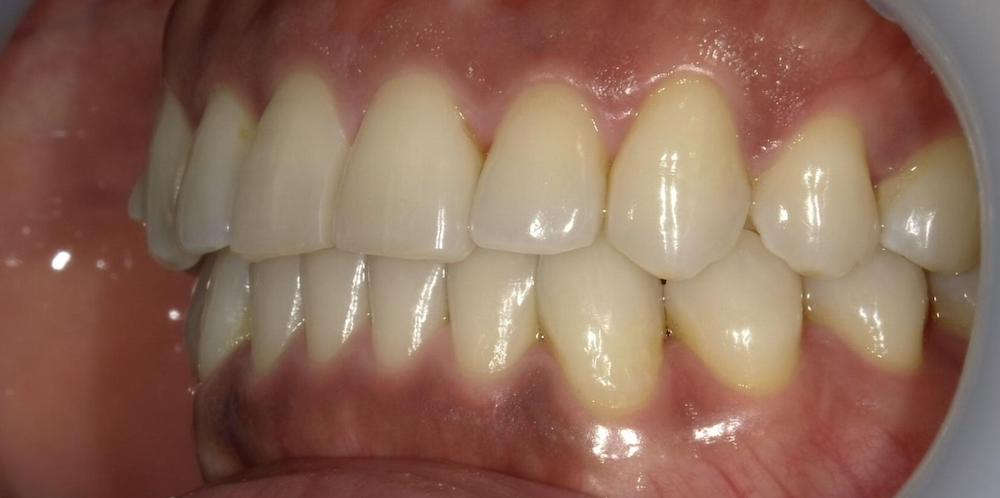

After

症例1 前歯の歯並びが後戻りによって出てきてしまったしまったケース(中等度)

10年ほど前のワイヤー矯正後に、保定装置をつけていなかったことが原因で前歯が後戻りしています。

- 治療方法 インビザライン上下+形態修正

- 治療期間:1年

- 治療費用 ¥759000(税込)

- 治療のリスク・デメリット 保定装置をしないと後戻りする